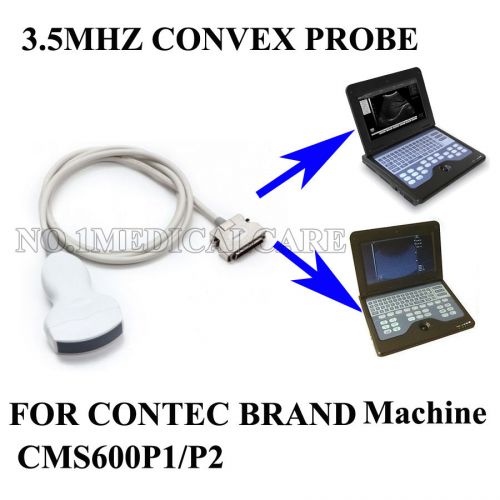

3.5mhz convex probe for Contec b ultrosound scanner CMS600P1/ CMS600P2

new 3.5mhz convex probe for Contec b ultrosound Diagnostic scanner